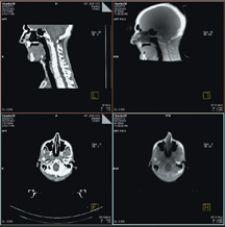

MVision, from Siemens Medical Solutions, is a volumetric in-line target imaging solution and the natural next step in Image-Guided Radiation Therapy (IGRT). Designed to work with Siemens’ linear accelerators, the system is the first commercial implementation of cone-beam technology utilizing a standard radiotherapy treatment beam. MVision makes it possible for the megavoltage (MV) source used for treatment to also create a 3-D image of the patient, enabling clinicians to “see inside” the patient at the most appropriate moment.

MVision fully integrates and automates all processes, including acquisition, reconstruction, registration, assessment, patient positioning and clinical review. With a few steps, therapists can calculate 3-D offsets, send them to the treatment couch to compensate for daily variations and safely deliver therapy.